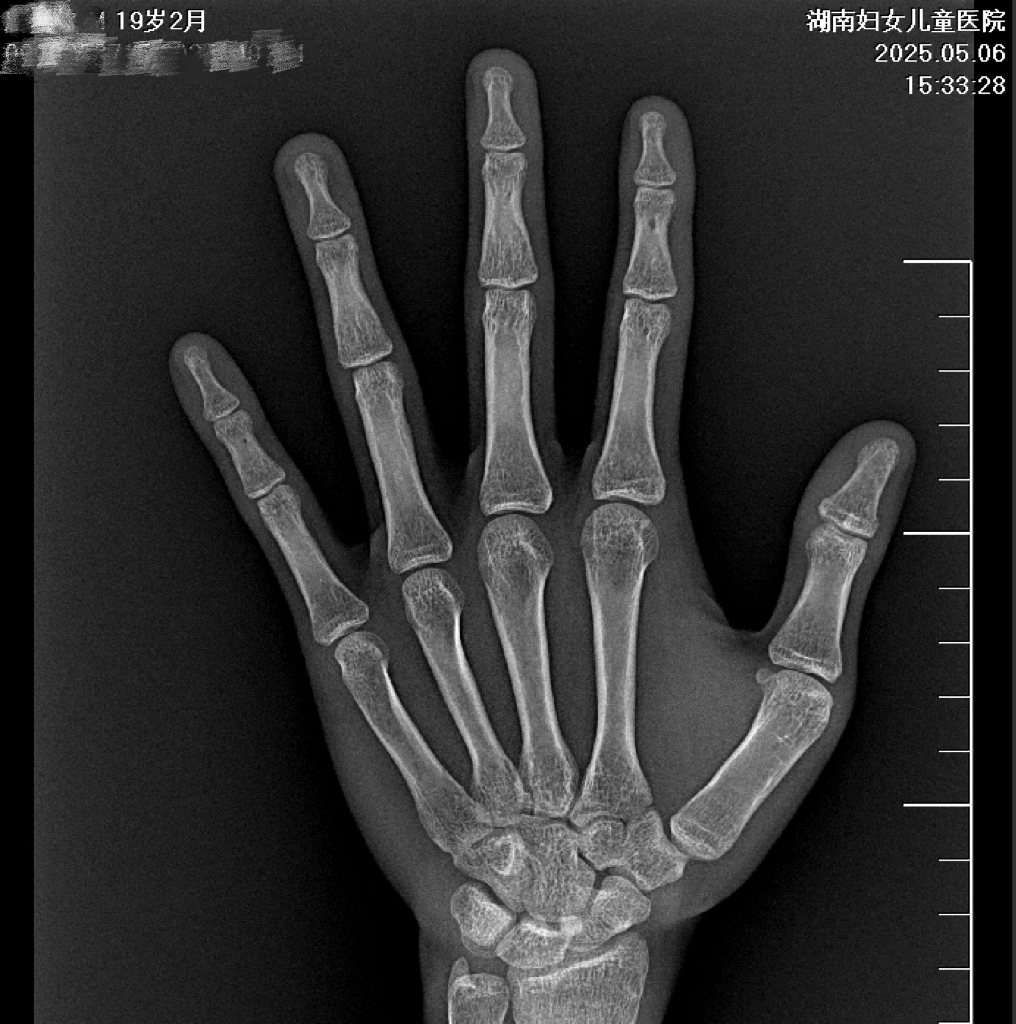

检查结果一出来就印证了医生的判断,「骨骺完全闭合、再无生长机会」,但小枫盯着报告单,满脸都是难以置信,一连串问题像连珠炮似的抛出来。得知自己 159.9 cm 的身高与 172.7 cm 的全国男性平均身高存在差距后,他久久沉默,眼神里满是失落与不甘。

小枫的遗憾就在于,从小到大从来都是自然生长,从未做过专业体检,更别说定期测骨龄了,所以当他所有第二性征都已成熟时,骨骺线已经闭合,生长板停止活动,再也没有长高的可能了。